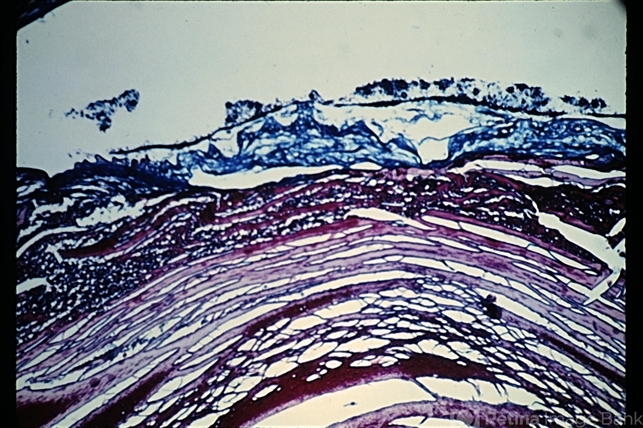

- anterior subcapsular polar cataract

- Anterior subcapsular cataract. The tissue stains as collagen. This process is an example of metaplasia of epithelial cells to connective tissue cells (trichrome stain x28). (Scheie Eye Institute, No. 5753.)